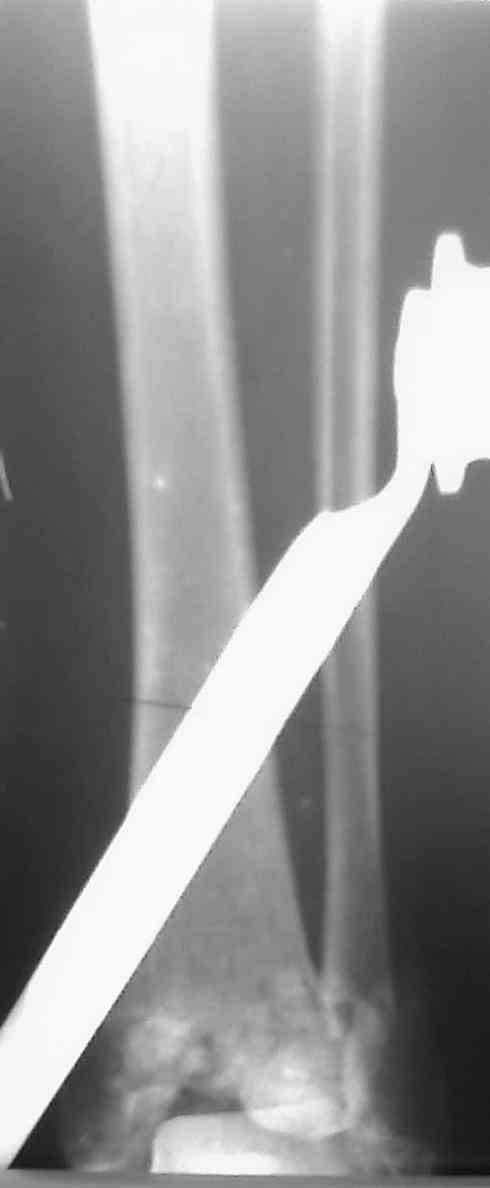

Снова приветствую вас, коллеги. К моменту вступления в обсуждение аксакалов, операция была, увы, выполнена(31.10.07.) Начали с доступа к наружной лодыжке, произвели ее фиксацию спицами, развернули кусок заднего края, наложили дистрактор, затем произвели дистракцию, фиксацию спицами дистального эпиметафиза б/бк,Рентгено-контроль. синтез наружной лодыжки 1/3пластиной. из двух коротких разрезов сформирован канал под медиальную тибиальную пластину LCP. Края ран ушиты без натяжения. Прочувствовать жесткость фиксации винтами с угловой стабильностью не удалось, поэтому дистрактор оставлен на энное время.

На представленных R-снимках не окончательный вид после остеосинтеза. Дистальная опора давила на стопу, пришлось ее сместить проксимально, в рез-те чего, она закрыла щель сустава, последние снимки не информативны.

Дистальные винты как-то чуть не все идут не в дистальные отломки, а в зону перелома. И действительно, присоединяюсь к вопросу Якова - в диафизе так и оставили 1 винт?

Мне тоже кажется, что имея в дистальном отломке один блокированный винт (в медиальной лодыжке), а остальные в зоне дефекта, где должна была бы быть костная пластика, стабильности ждать не приходится.